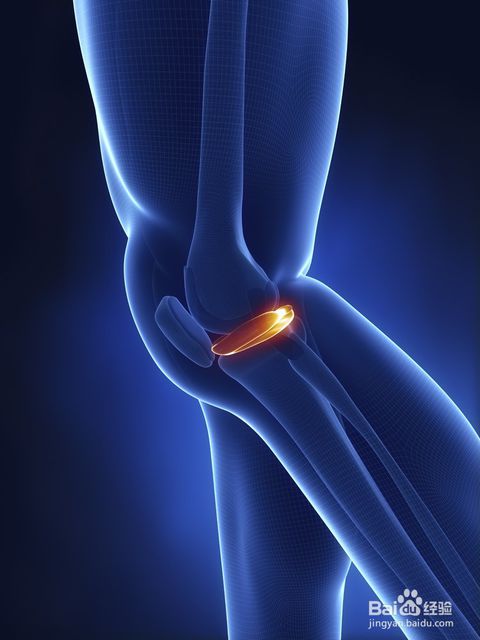

骨质增生症又称为增生性骨关节炎、骨性关节炎(OA)、退变性关节病、老年性关节炎、肥大性关节炎,是由于构成关节的软骨、椎间盘、韧带等软组织变性、退化,关节边缘形成骨刺,滑膜肥厚等变化,而出现骨破坏,引起继发性的骨质增生,导致关节变形,当受到异常载荷时,引起关节疼痛,活动受限等症状的一种疾病。

1. 病理学:不规则的软骨损害,在负重区域的软骨下骨硬化、囊肿,边缘骨赘增生,干骺端血流增加及不同程度的滑膜炎。

2. 组织学:早期软骨表面碎裂、软骨细胞增生、软骨面纵向裂开、结晶沉积,同时存在着软骨修复、骨赘增生;晚期出现软骨的彻底破坏,表现为软骨硬化、软骨消失及软骨下局灶性骨坏死。

3. 生物力学:关节软骨的可伸张性、抗压力、抗剪切力及软骨通透性降低。软骨水分增加,过度肿胀,软骨下骨硬化。